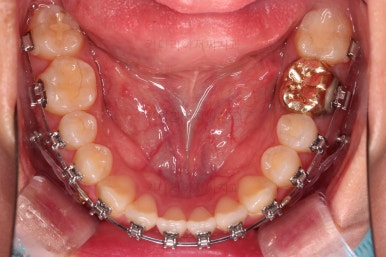

5. 치료의 종료

부산치아교정잘하는곳 키다리아저씨치과에서 치료를 종료했을 때의 사진입니다.

위아랫니가 가지런해졌고요.

보철 치아의 위치/크기로 인해 100% 중앙선은 맞기 힘드나 가장 잘 맞추어 놨고, 앞니의 각도도 매우 좋아졌습니다.

아래 앞니도 단순히 머리 부분만 뒤로 눕힌 것이 아니라 뿌리까지 뒤로 당겨왔고요.

교합, 가지런함, 앞니 각도 모두 좋아졌습니다.